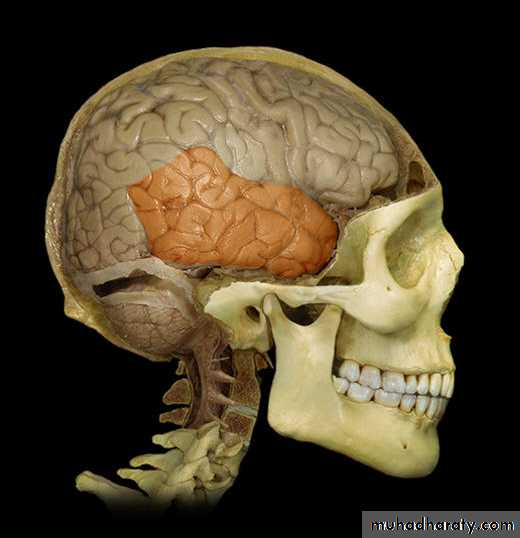

Lobes of Cerebral Hemisphere

Five lobes

Frontal lobe

Parietal lobe

Temporal lobe

Occipital lobe

Insular lobe

Parietal lobeOccipital lobe